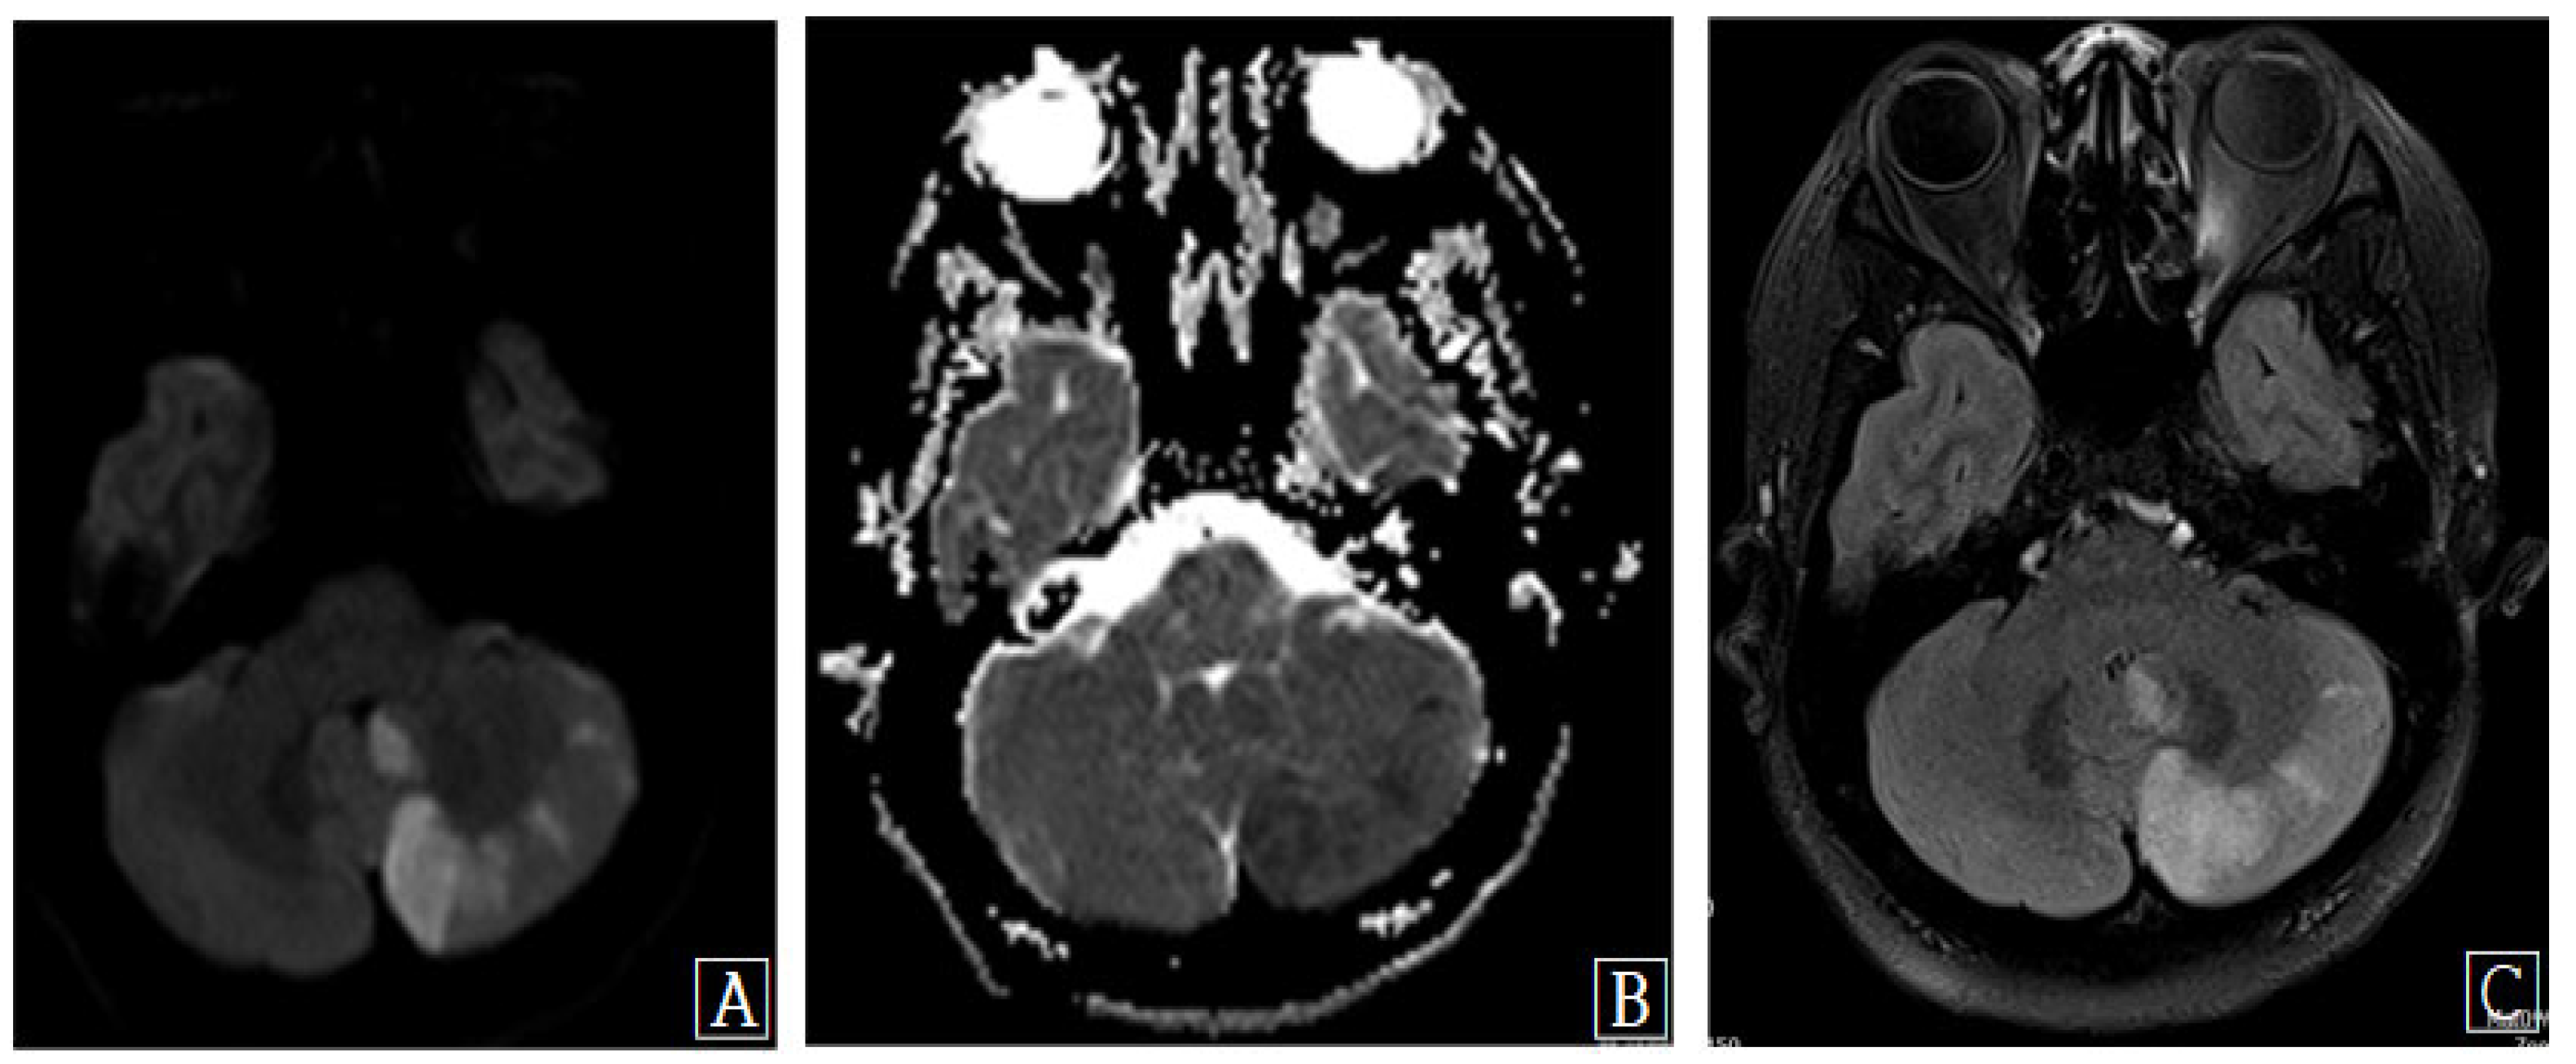

Figure 2. Brain magnetic resonance (MR) images show multiple patchy foci of diffusion restriction, consistent with acute left posterior inferior cerebellar artery territory infarction. (A) Diffusion-weighted MR image. (B) Apparent diffusion coefficient MR image. (C) Axial T2 flair MR image. Uneventful surgery was performed in the usual manner using a right-sided retropharyngeal approach. General anesthesia was uncomplicated, and intraoperative bleeding was well controlled, with a total blood loss of <140 mL. During the surgical procedure, the blood pressure was stable, remaining between 90 and 130 mmHg. No episodes of excessive flexion, extension, or lateral rotation occurred at any stage of the procedure. She awoke from the anesthetic neurologically intact; however, 14 h later, she complained of severe headache, dizziness, and diplopia. Urgent MRI of the cervical spine and brain was performed. MRI of the cervical spine showed satisfactory decompression of the cord and foramen; however, a large left inferior cerebellar signal abnormality indicating an acute cerebellar infarction was found on brain MRI (Figure 2).